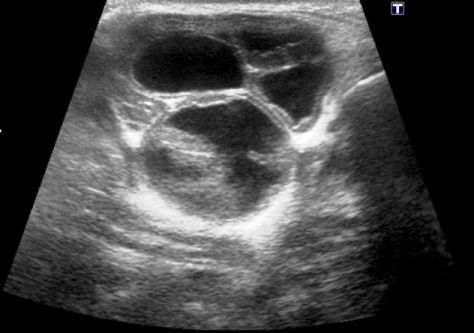

Ultrasound of the neck was ordered to determine the composition of the swelling. Findings included bilateral parotid masses identified as enlarged parotid glands with multiple 2- to 3-cm cysts present within the glandular tissue (Figures 1-3).

Figure 3.